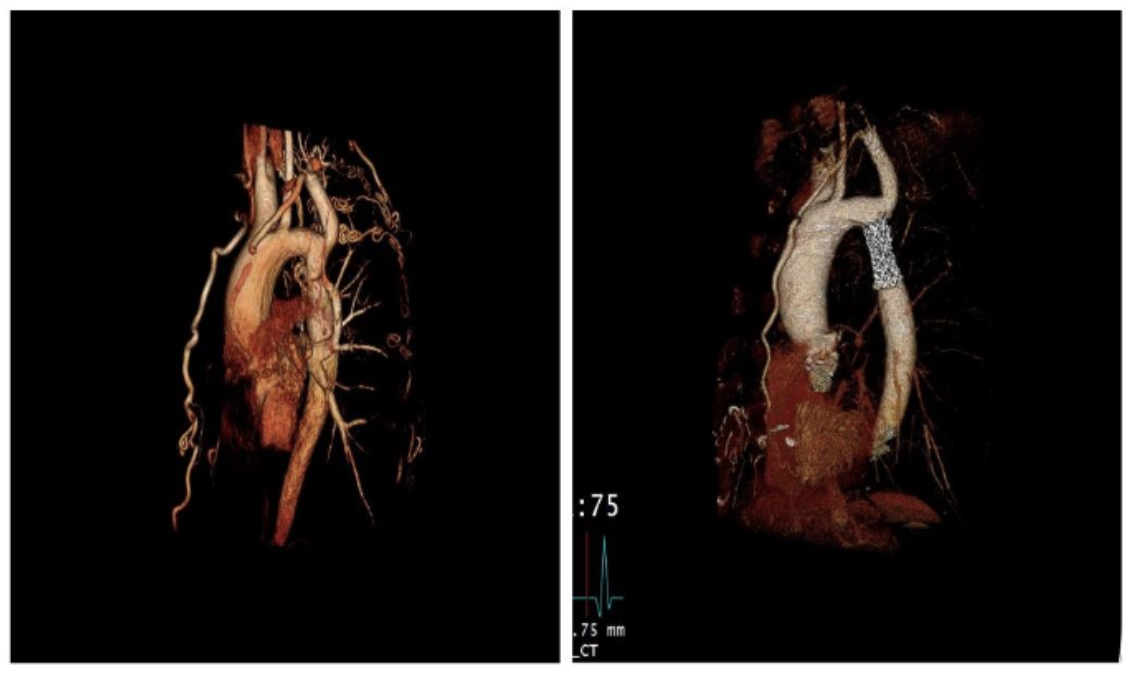

Volumetric measurements were taken from baseline and follow-up CT/MR studies with the 3D volume navigation function using the iNtuition program with 5 segments of interest (Figure B in Supplemental material).

Aortic volumetric measurements. Average time from the procedure to first follow-up CT/MR was 1.0 years (SD=1.5 years). A total of 38 paired CT/MR scans were used to obtain aortic volumetric measurements (paired pre- and post-operative CT image seen in Supplemental material, Figure D). No significant differences were found in baseline characteristics when comparing these 20 patients to the total sample other than proportion of patients with BAV (P<.05), as seen in Supplemental material, Table C. A significant reduction in aortic volume was seen along the ascending aorta, the aortic arch, and the area immediately proximal to the stent (P=.009, P=.001, P=.002, respectively) exhibited in Table 3. All stent lumen volumetric measurements were also found to be significantly reduced from baseline. The segment of aorta with the largest volume was the ascending aorta, followed by the aortic arch and the proximal descending aorta (descending aorta 1). All 38 patients with paired CT/MR scans were plotted in a spaghetti plot to show the difference in postprocedural and baseline aortic volume (Figure 3.)